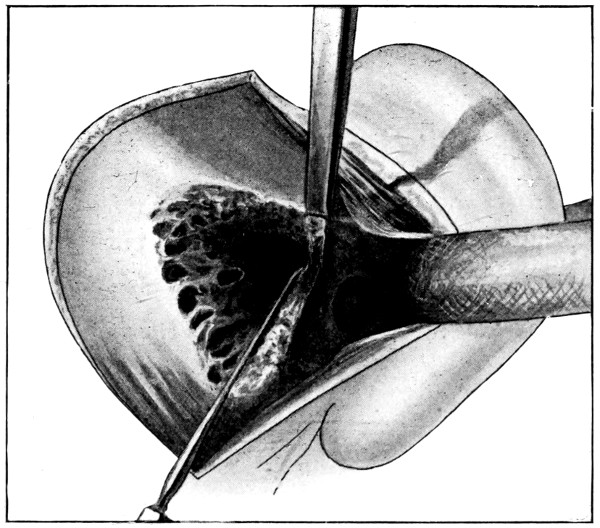

Between these two trephine-holes the dura mater is separated from the bone and the special director introduced, entering at the one hole, emerging at the other, and lying throughout between the dura and the bone. The saw is now passed along the groove of the director, the handles affixed, and the bone intervening between the two trephine-holes divided, not straight out to the surface, but bevelled or cut in such an oblique manner that the bone-flap, when replaced, rests on a ledge (see Figs. 17-19). The sawing process[26] generates considerable heat, and the assistant should be instructed to keep up irrigation with saline solution or sterilized water. The sawing is carried out by steady side-to-side traction, without jerks; if the saw breaks, the special handle may be attached, thus obviating the necessity of introducing a new saw.

Fig. 17. First Stage in the Formation of an Osteoplastic Flap. Gigli’s saw, protected from the dura mater by the special director, passing between the two trephine-holes. For further description, see text.